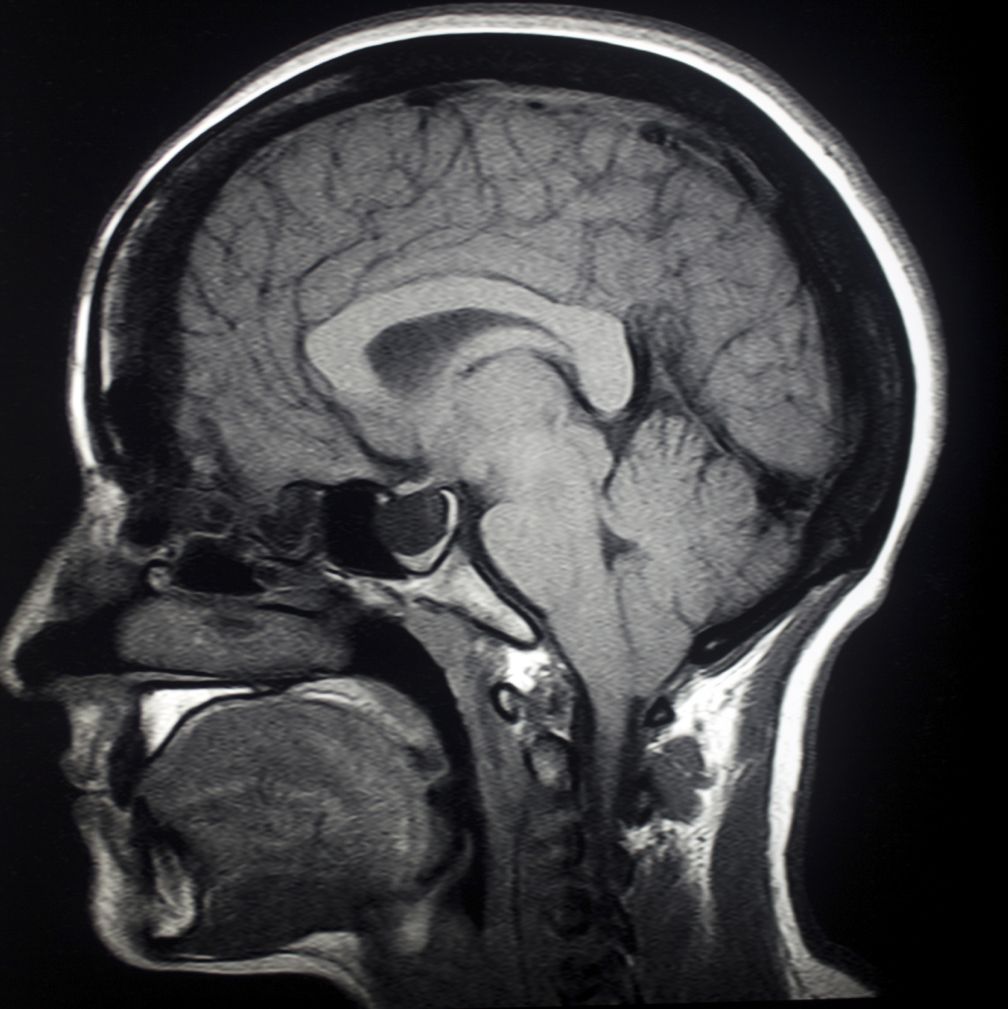

Lista muestra hermosas imágenes de resonancia magnética cerebral normal y anormal dinosenglish.edu.vn para que puedas explorar más en detalle.

resonancia magnética cerebral normal y anormal Pin en NEUROCIENCIAS resonancia magnética de cerebro Resonancia magnética (RM) de cerebro, corte axial ponderado en T2: la … VIDEO Nueva mancha en la Resonancia

Engineer Team : RESONANCIA MAGNETICA Magnetic Resonance Imaging – Clinical Images Hallazgos por resonancia magnética cerebral de nuestro paciente. M, 21 … Imágenes por resonancia magnética anormales como predictoras de mal … Imágenes por resonancia magnética anormales como predictoras de mal … Lesiones en resonancia magnética (RM) del encéfalo y la médula espinal … Pin en Resonancia Magnética del Encéfalo A) Resonancia magnética cerebral (RMC) mostrando infartos en … Caso 1: Edema cerebral visualizado mediante RM. (A) Secuencia T1 plano … Rascacielos dormir pasta tac y resonancia diferencias retrasar … Pin on Apuntes de Enfermería y T.C.A.E Resonancia magnética cerebral secuencia T2, que muestra lesión … Meningitis aguda en la enfermedad de Behçet | Reumatología Clínica Resonancia magnética coronal normal del cerebro Fotografía de stock – Alamy Imágenes de resonancia magnética, la imagen de la cabeza en diferentes … Resonancia magnética cerebral A) protocolo T1 sagital (Caso 1). Se … Resonancia magnética cerebral. Secuencia T1 corte sagital. Atrofia … Resonancia magnética de cerebro, cortes axiales, secuencias T2. Señal … Resonancia magnética de cráneo. A y B) Cortes axiales FLAIR … Resonancia magnética (RM) de cerebro, corte axial ponderado en T2: la … RM cerebral: Interpretación paso a paso | Kenhub Resonancia magnética de cerebro, cortes axiales, secuencias T2. Señal … De Resonancia Magnética De Cerebro Foto de archivo – Imagen de arteria … Top 107+ Imagenes de resonancia cerebral normal – Destinomexico.mx -Imagen por resonancia magnética del cerebro. a) Cortes sagital y axial … resonanCia magnétiCa Cerebral donde se observa hiperintensidad a nivel … MRI (Imagen de resonancia magnética) – Tomografía computarizada de la … Meningioma – NCI Imágenes por resonancia magnética coloreadas del cerebro sano del … Resonancia magnética cerebral en secuencia FLAIR, que muestra lesiones … Contraste resonancia magnetica cerebral – senturinthegreen Relación de los espacios de Virchow-Robin con la enfermedad de … Gliomatosis cerebral – Instituto Nacional del Cáncer Pin en Neurology. Recomendaciones para la utilización e interpretación de los estudios de … Fotografía De La Proyección De Imagen De Resonancia Magnética Del … atmósfera Dirigir Cumplir anatomia resonancia magnetica Desarrollar … Pin en #MEDICINA,#SALUD Resonancia magnética de la nasofaringe De Resonancia Magnética De Cerebro Foto de archivo – Imagen de polilla … Atrofia cortical global de predominio parietal en la Resonancia … Resonancia magnética cerebral | Download Scientific Diagram Neuroblog: Resonancia magnética cerebral en la trombosis crónica de … De Resonancia Magnética De Cerebro Imagen de archivo – Imagen de … ¿Cuáles son los riesgos de la resonancia magnética? – Integra Salud … Resonancia magnética cerebral al decimocuarto día de ingreso: área … Resonancia magnética. Corte axial mostrando área infartada en el … Resonancia magnética cerebral del paciente AV evidenciando lesiones en … -Ressonância magnética de encéfalo mostrando múltiplas imagens … Resonancia magnética cerebral secuencia FLAIR (Fluid Attenuated … Resonancia magnética cerebral con protocolo de epilepsia, en sección … Resonancia magnética cerebral en corte sagital. Se observa una evidente … Resonancia magnética craneal en la que se evidencian lesiones … Logran visualizar el cerebro a detalle más completo tras una resonancia … Así decide el cerebro la severidad de un castigo De Resonancia Magnética De Cerebro, Imagen de archivo – Imagen de … A) Resonancia magnética cerebral; Secuencia Tof: oclusión de arteria … Un estudio asocia la ansiedad con la aparición rápida del Alzheimer IMÁGENES DE 18 F-PR04.MZ PET FUSIONADA CON RESONANCIA MAGNÉTICA … Imágenes por resonancia magnética anormales como predictoras de mal … Tumores de la región pineal – Instituto Nacional del Cáncer Epilepsia: una historia de voces y fantasmas | Neurología Contribución de las imágenes de resonancia magnética por tensor de … Resonancia magnética secuencia T2 plano coronal de quiste epidermoide … Resonancia Magnética Cerebral del paciente: a. Aumento de… | Download … Resonancia magnética cerebral 2022 Síndrome de hemiconvulsión-hemiplejía-epilepsia. Seguimiento de un caso … Enfoque Radiologico: La resonancia magnética permite detectar lesiones … Resonancia magnética craneal T1 con contraste que muestra angiomatosis … guidewiz – Blog Resonancia magnética cerebral, secuencia SWI. Ribete hipointenso en la … resonAnCiA mAgnétiCA de ColumnA Con gAdolinio. Corte sAgitAl en t1 de … SEMANA 12: FUNDAMENTOS DE RESONANCIA MAGNÉTICA NUCLEAR. INDICACIONES Y … DIAGNÓSTICO DE ESCLEROSIS MÚLTIP Magnetic resonance imaging of the brain – Alchetron, the free social … Resonancia magnética de órbitas | Instituto Radiológico Dr. E Castillo Alteración de la marcha en un paciente post-trasplante hepático Resonancia magnética cerebral de un paciente sano (Ay B) y paciente que … Utilidad de la resonancia magnética craneal para el diagnóstico de la … Resonancia Magnética Del Cerebro El Tumor Cerebral Foto de stock y más … De Resonancia Magnética De Cerebro Imagen de archivo – Imagen de … ABDALLA RADIOLOGIA: NEURINOMA ACUSTICO Atrofia cortical global de predominio parietal en la Resonancia … Resonancia Magnética : Producción de la imagen MRI Brain Scan — Stock Photo © Bunyos30 #18724051 Mri (imagen de resonancia magnética) Monitor con imagen de captura de … Tomografía computarizada vs resonancia magnética: diferencia y … Tumores Cerebrales – Unidad de Neurocirugía RGS Resonancia magnética de la columna, sección sagital. Observe los discos … La resonancia magnética, una técnica imprescindible en el diagnóstico … Perfusión Cerebral por Resonancia Magnética | ¿Qué es? ¿Necesita Contraste? Resonancia Magnética Cerebro A: resonancia magnética, T2 coronal preoperatoria; se observa lesión en … Resonancia magnética cerebral — Foto de stock © Bunyos30 #27340623 La resonancia magnética se perfila como detector de mentiras | Futuro … Resonancia magnética cerebral en T1 con gadolinio, cortes axial (a … MRI brain : show brain tumor at right parietal lobe of cerebrum — Stock … NEUROIMÁGENES EN ENFERMEDAD DE PARKINSON: ROL DE LA RESONANCIA …